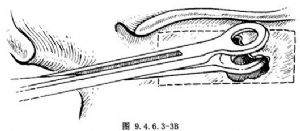

再用Luc咬骨鉗咬去穿刺的後上及後下骨壁(圖9.4.6.3-3)。